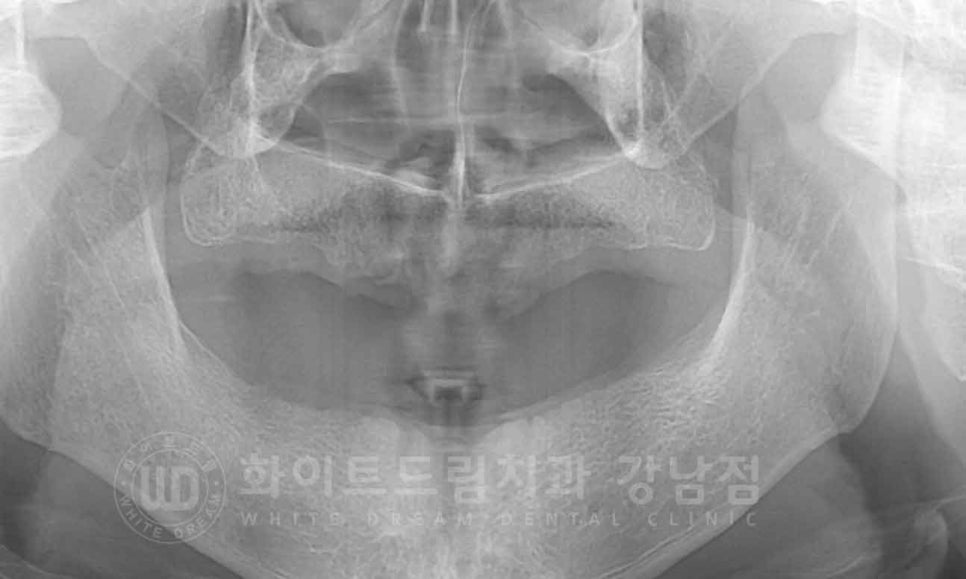

▲ 발치 후 x-ray입니다. 치아 뿌리까지도 깔끔하게 발치가 되었습니다.

잇몸 회복 기간 동안 임시틀니를 사용하시며 지내시게 됩니다.

이 회복 기간 동안 잇몸에 남아있던 염증도 가라앉히고

잇몸의 상태를 임플란트 식립을 하기 위한 적절한 상태로 변화시켜 주는 것이죠.